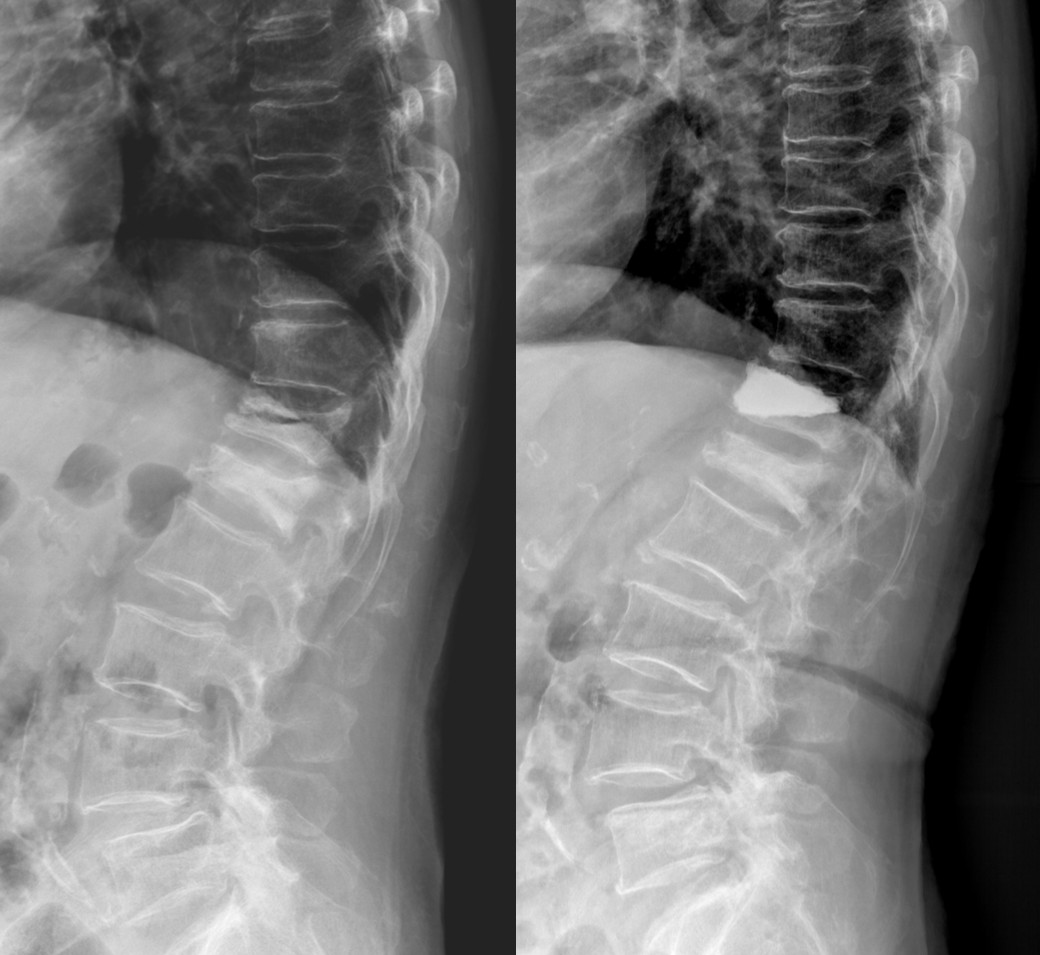

手術後從X光可以見到椎體骨折的裂隙被骨水泥填充,甚至椎體的高度也比術前恢復。

| 椎體成型術前與術後X-ray |